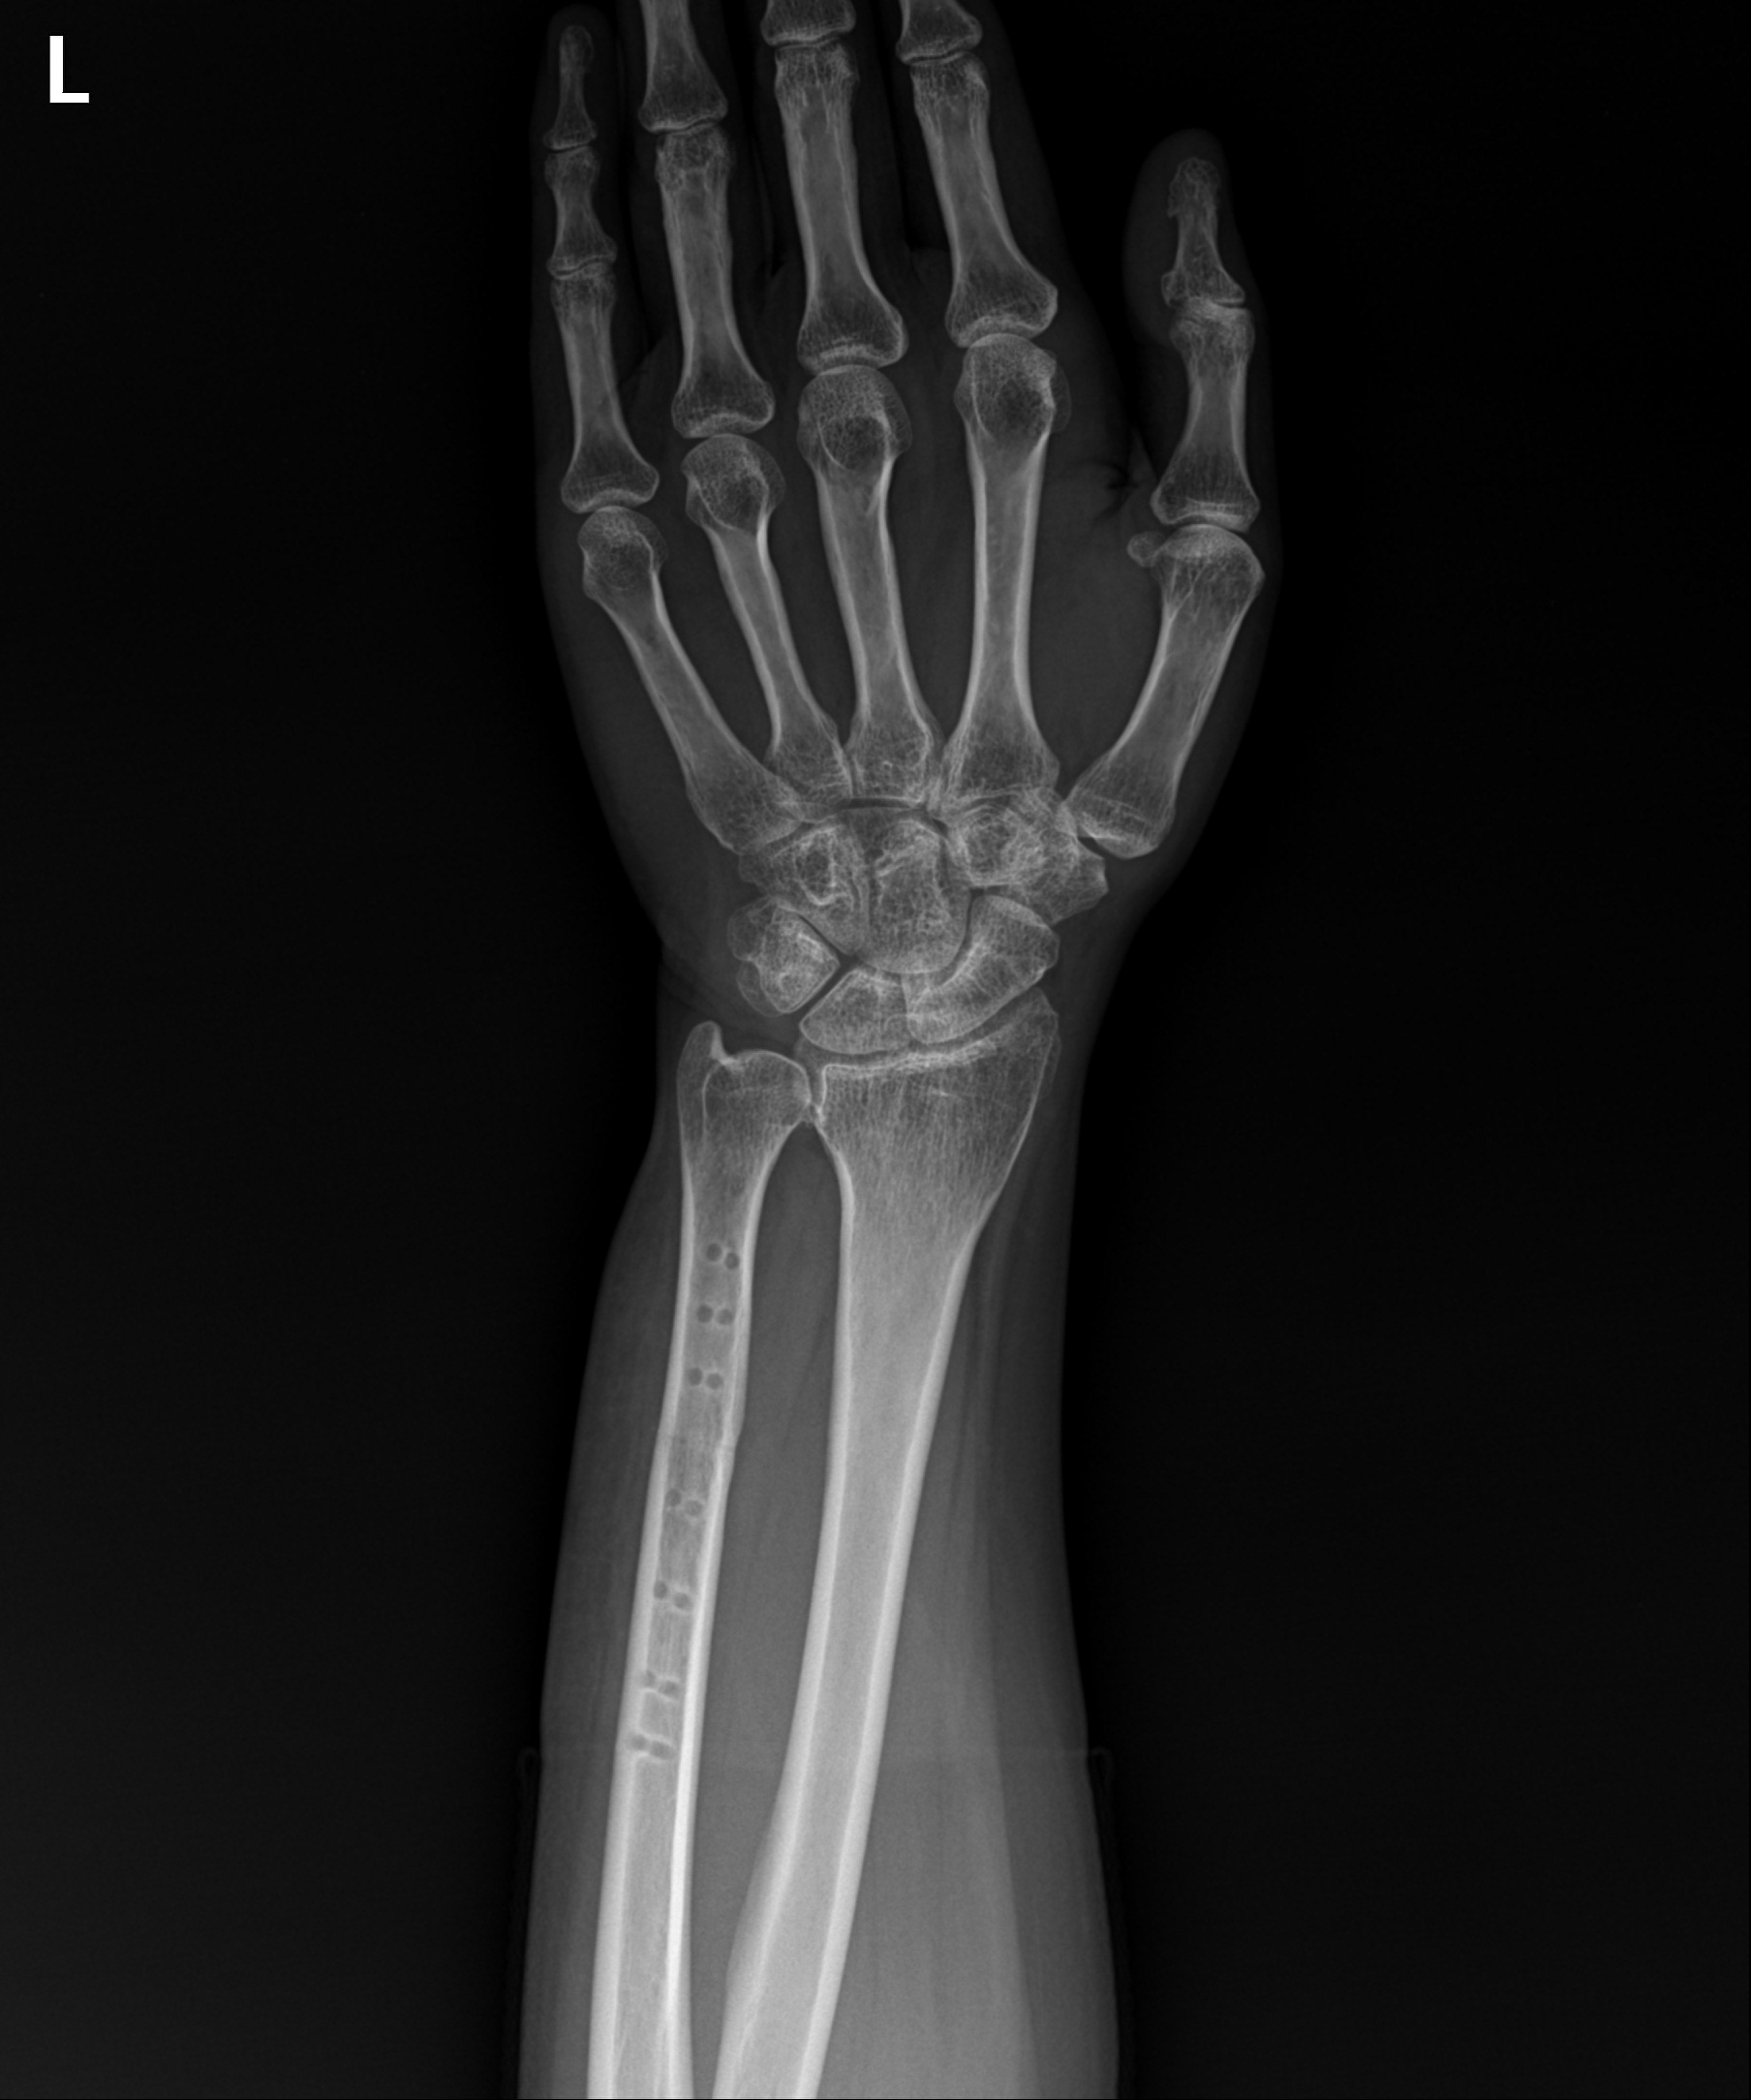

척골이 길어진 모습

2021.11.29